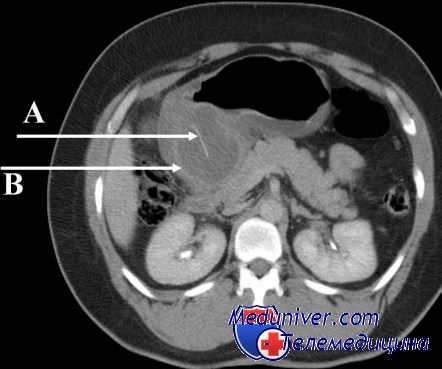

- Контрастная рентгенография брюшной полости. Выполнение серии рентгенограмм после перорального контрастирования подтверждает заброс и длительную задержку контрастного вещества в просвете приводящей петли, рубцовую деформацию в области анастомоза. Могут определяться признаки атонии тонкого кишечника.